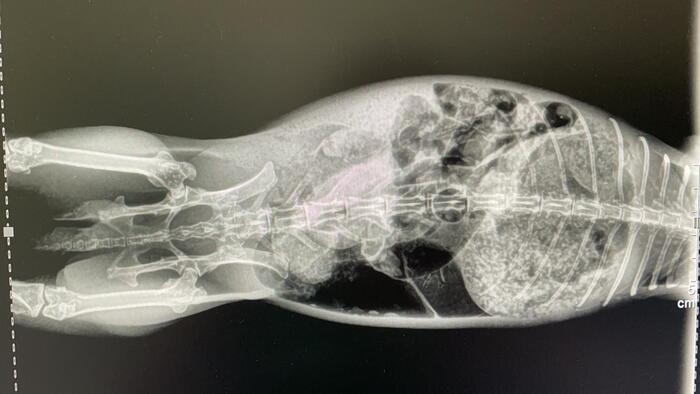

Piedras riñones / vejiga

Este es el caso de un conejito que sufría de colapso en la vejiga, como podréis ver en las radiografías tiene una cálculo enorme que le ocupa la vejiga entera, esto le producía un gran dolor y la imposibilidad de orinar, por lo que los riñones sufrían riesgo de colapso en cualquier momento. Tenía graves problemas digestivos también causados por dolor y por una parálisis en el intestino (íleo paralítico), algo que es muy grave en conejos, no podía digerir bien la comida y dejó de comer, antes de ello tuvo diarrea un tiempo.